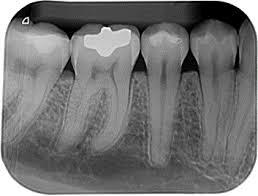

• Rayos X.

Rayos X.

Wilhelm Conrad Rontgen descubrió los rayos X en 1895 y el Dr. C. Edmund Kells implicó este nuevo descubrimiento a la odontología.